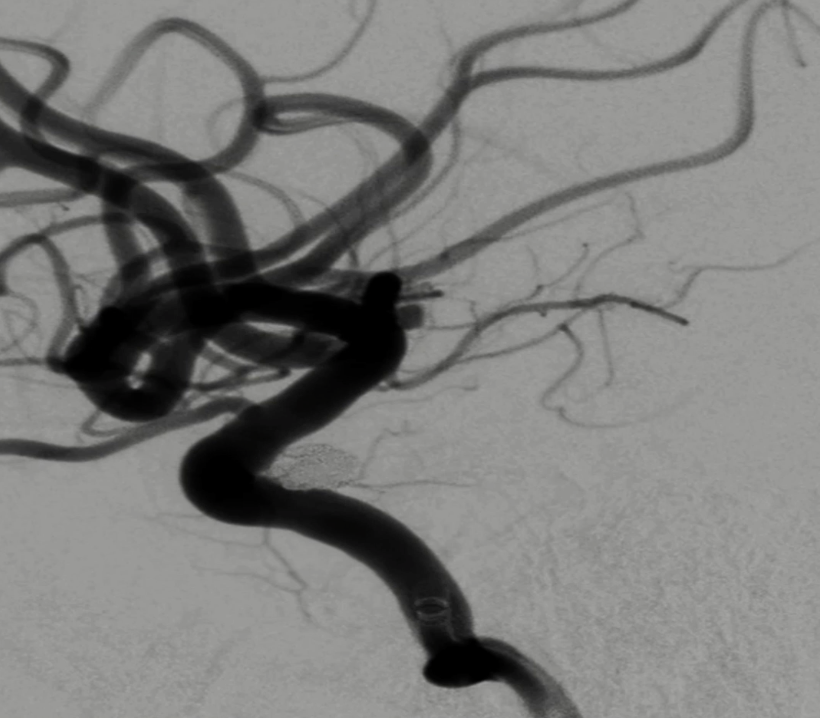

继续填入Target 1.5/2弹簧圈成篮,后完全释放支架,其近端位于颈内动脉分叉处,远端位于A1远端。

填入第一枚弹簧圈

通过调整栓塞微导管的张力继续填入Target 1/3弹簧圈。

术后正侧位造影:Raymond Ⅲ级

术后支架重建:支架打开良好,近端Marker位于颈内动脉分叉处